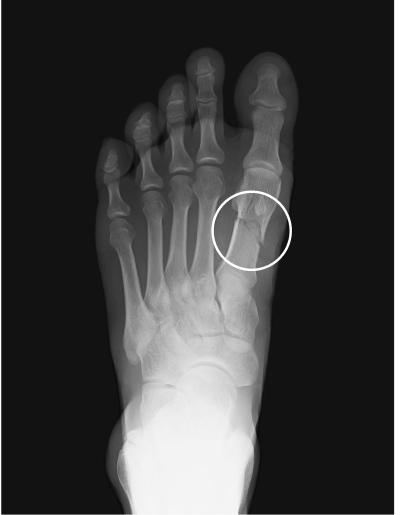

Metatarsal fracture

age 16

age 13